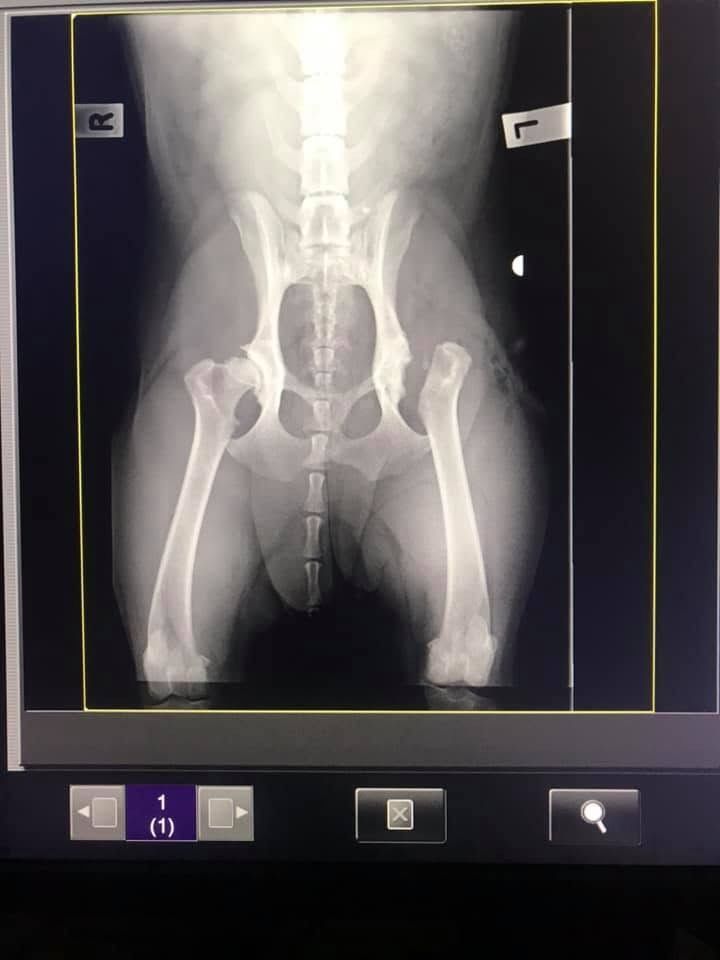

Orthopaedic Surgery: Restoring Mobility & Comfort

Orthopaedic issues, such as fractures or ligament injuries, can significantly affect your pet’s quality of life. At Kanwal Veterinary Hospital, we offer specialised orthopaedic surgery to address these challenges and restore your pet’s mobility. Using advanced techniques and equipment, our experienced team ensures the best possible outcomes for your furry friend.

From stabilising broken bones to correcting joint problems, our orthopaedic procedures are tailored to each pet’s unique condition. We take a personalised approach to pre- and post-operative care, ensuring your pet receives the support they need for a smooth recovery.